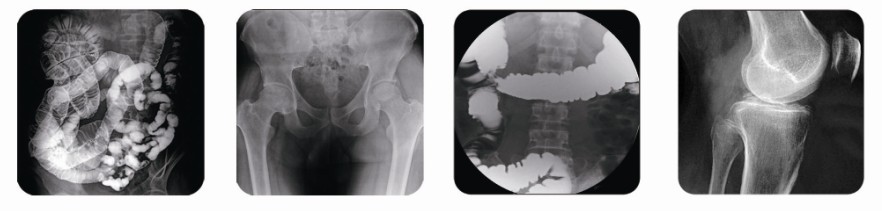

胃腸檢測儀屬于醫(yī)院的高端醫(yī)療設(shè)備,目前市場中銷售的有200毫安胃腸設(shè)備、500毫安胃腸設(shè)備、800毫安胃腸設(shè)備等,其中又以800毫安胃腸設(shè)備較為主流。那么一臺800毫安胃腸設(shè)備多少錢?

目前國內(nèi)800毫安胃腸設(shè)備生產(chǎn)廠家中,普朗醫(yī)療屬于知名品牌。普朗醫(yī)療這臺800毫安胃腸設(shè)備主要應(yīng)用在頭顱攝影、食道造影、消化道檢查、支氣管造影、胃腸造影、胸部攝影、脊髓造影、靜脈造影、泌尿系統(tǒng)造影、子宮輸卵管造影、兒科影像檢查、介入放射治療應(yīng)用等。應(yīng)用范圍非常廣泛,是醫(yī)院及相關(guān)部門的首選胃腸設(shè)備點擊圖片下方紅字了解更多。

(普朗醫(yī)療——高頻數(shù)字化醫(yī)用診斷X射線機PLD6800800毫安胃腸設(shè)備))